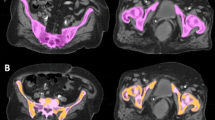

The pelvic bone marrow was defined as the contoured volumes of L4, L5, proximal femur to lesser trochanter, ilium, sacrum, ischium, and pubis using total bone as a surrogate for bone marrow, as seen in Fig. 1a. The APBM was created by first calculating the whole body mean standard uptake value (SUVwb) using the initial pretreatment PET/CT. This was done by generating a whole body contour then creating a constraint to only include the SUVs that were greater than the mean SUVwb, producing a volume defined as the constrained uptake (CU), as can be seen in Fig. 1b. The PET/CT was fused to the planning CT using MIMvista (Mimvista, Cleveland, OH) deformable registration algorithm, which was accomplished in a systematic workflow designed for this study. RegRefine was used to lock in on stable positions (sacrum and iliac crests) on the pelvis to minimize inter-patient variability in the fusion. The CU volume was transferred to the planning CT and was used to selectively isolate the bone marrow sub-volume from the PBM. The APBM volume was defined as the union of CU volume with the PBM volume (Fig. 2). The PBM and APBM volumes were collected, and the APBM/PBM fraction was calculated.